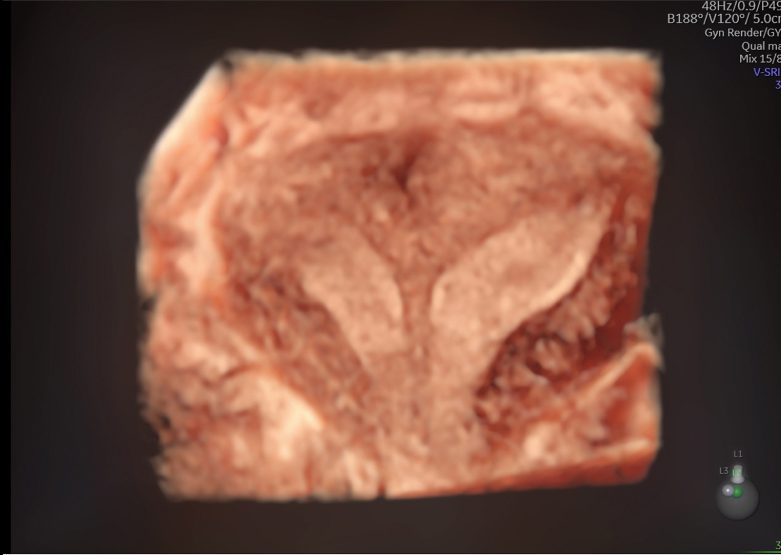

Imagens clínicas

Imagens 2D e 3D/4D de próximo nível

Imagens clínicas

Imagens 2D e 3D/4D de próximo nível